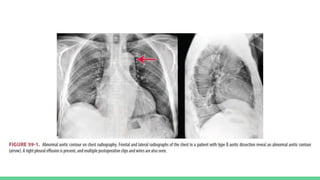

● CHEST X RAY - Most common radiographic abnormality is widened

mediastinum (or) abnormal aortic contour

Other possible findings include

pleural effusion

Displacement of aortic intimal calcification

Deviation of trachea , mainstream bronchi , or esophagus